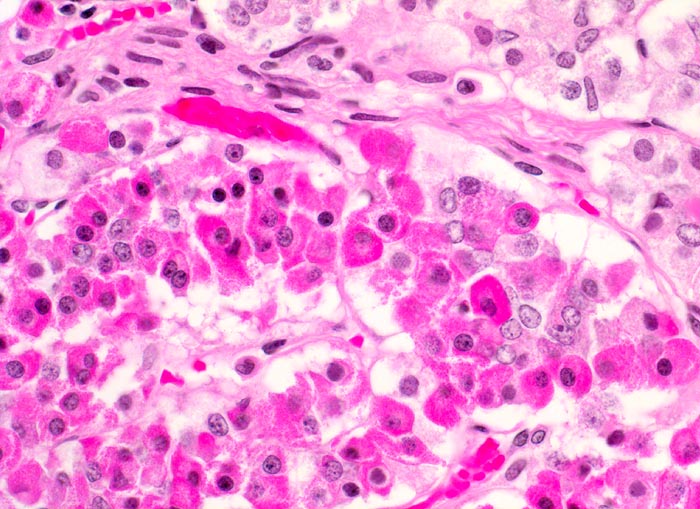

PathoPic – image database / PathoPic ID 4132 - Adenohypophyse

Adenohypophyse

Adenohypophyse mit verschiedenen Zelltypen. Die Zellen haben unterschiedlich gefärbtes Zytoplasma. In der HE Färbung können Azidophile, Basophile und Chromophobe Zellen nicht sicher voneinander abgegrenzt werden.

400